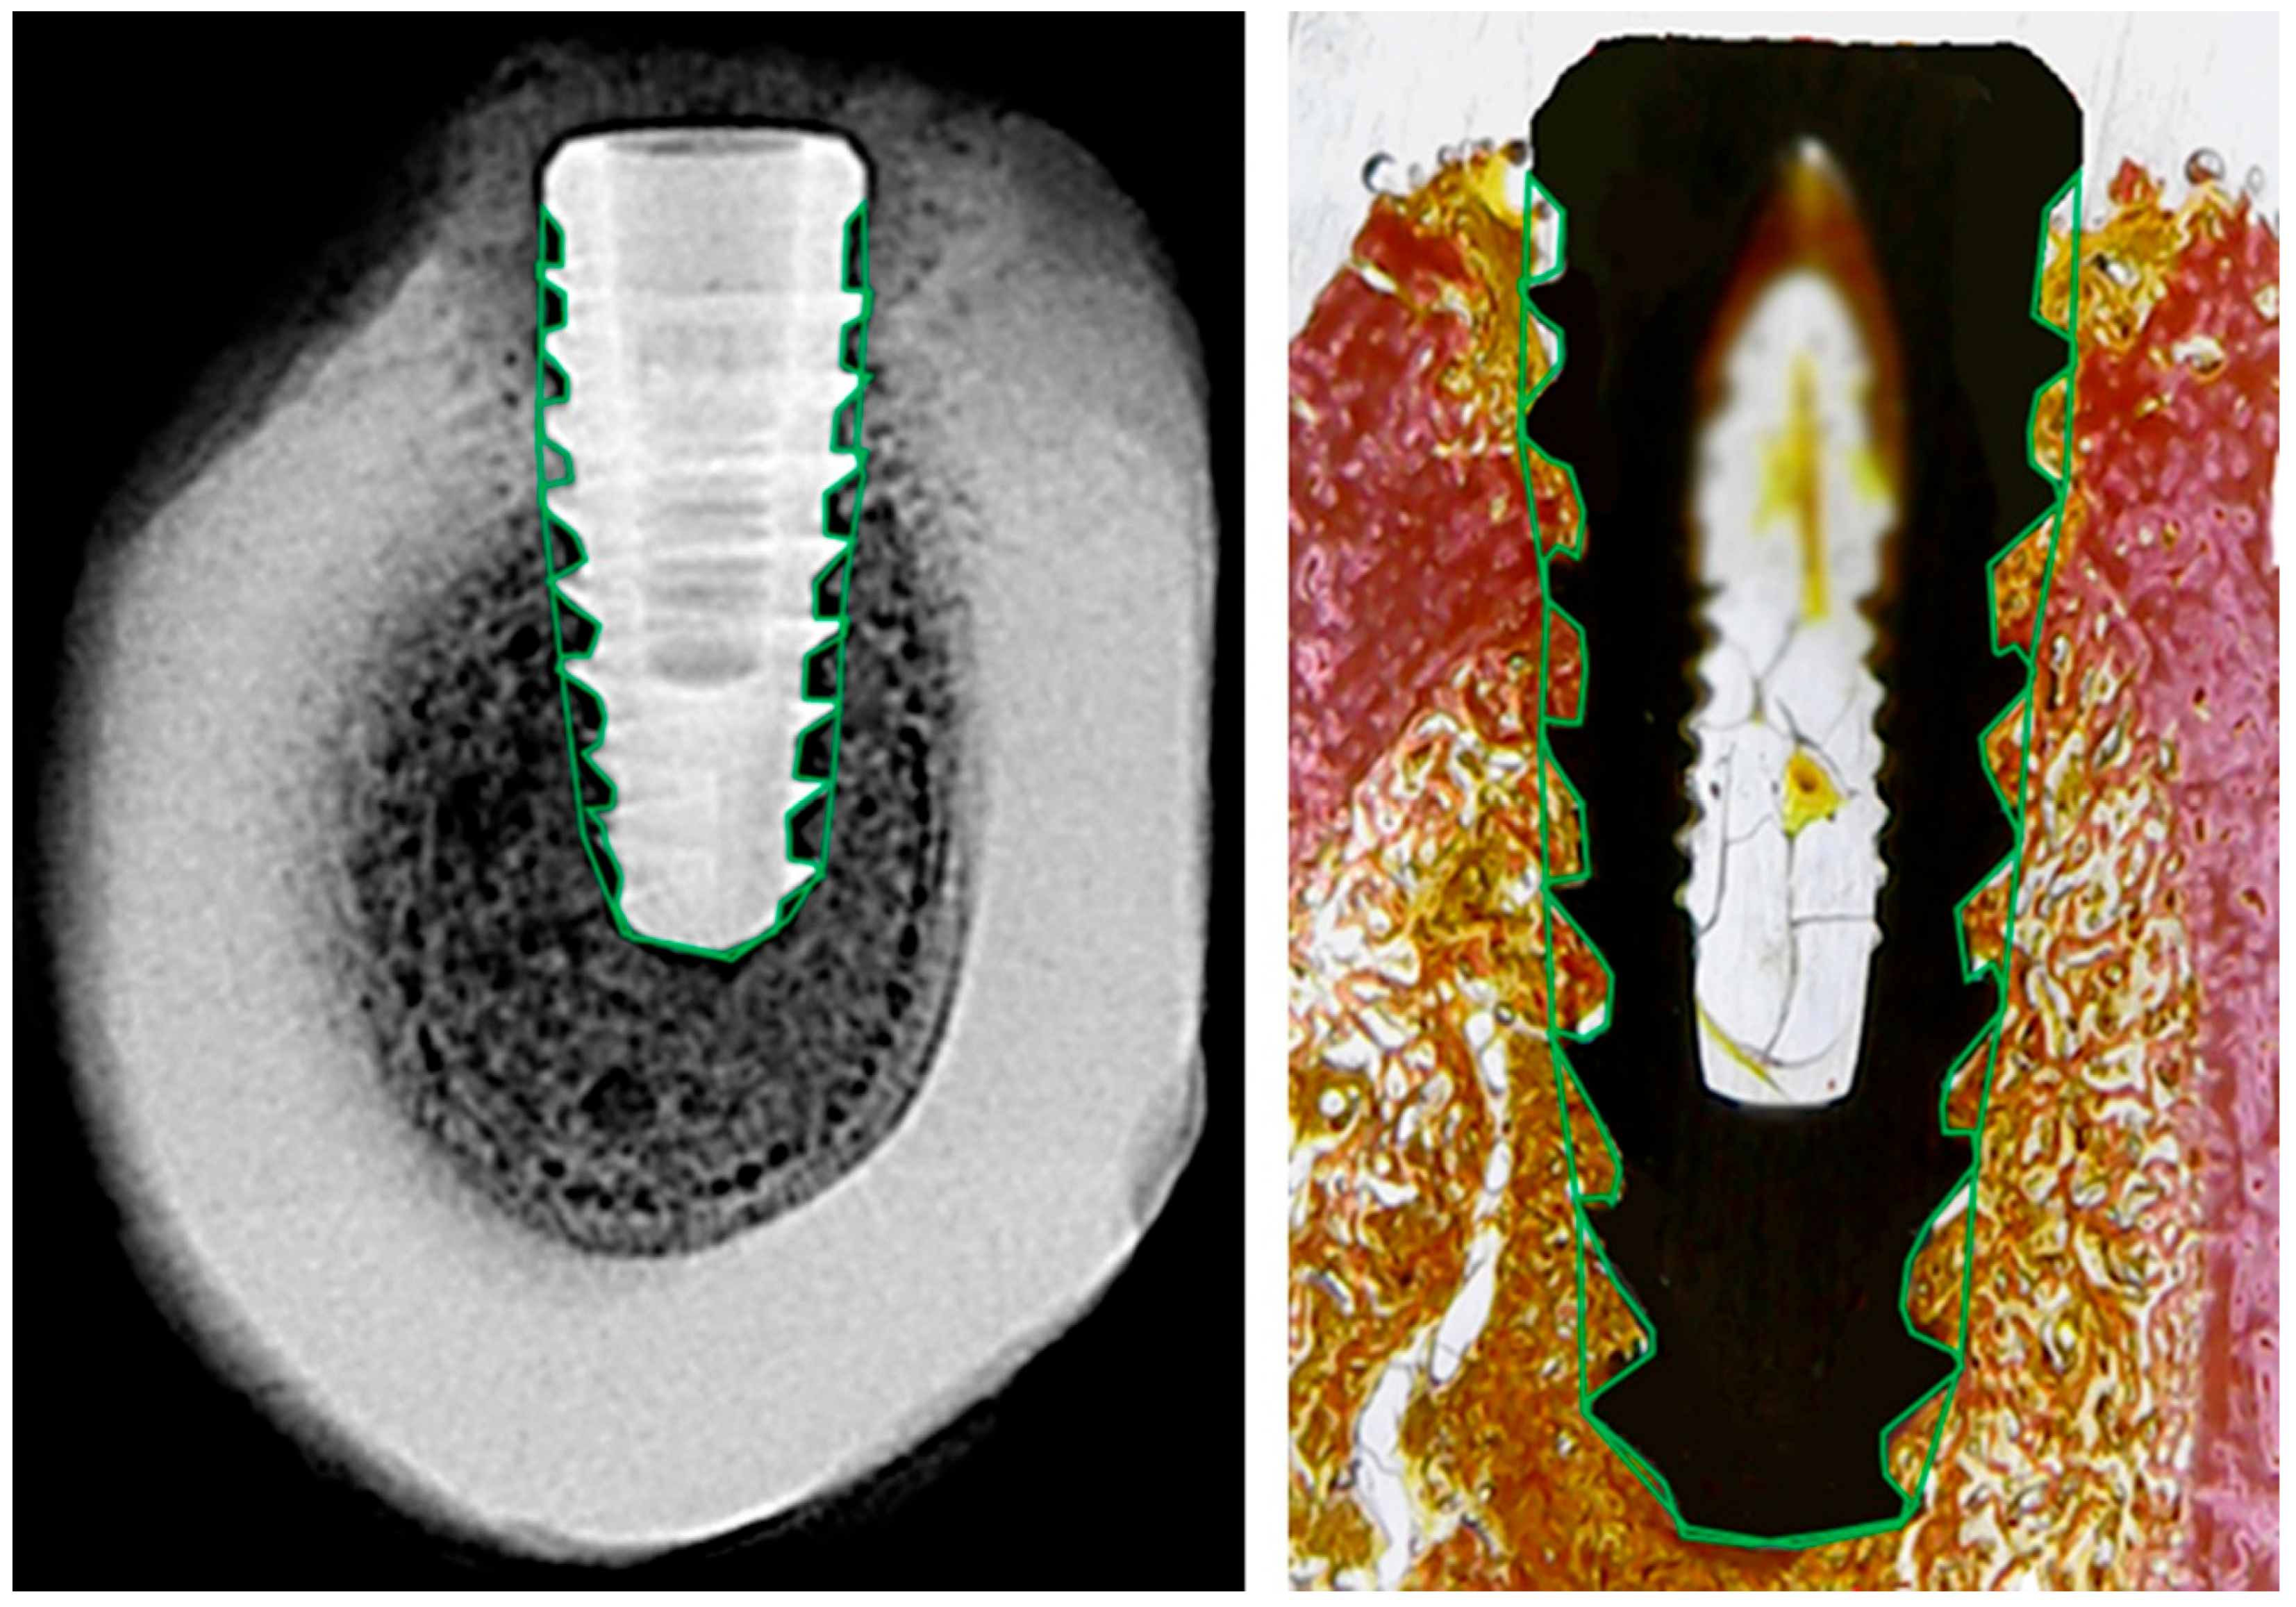

Radiographic and histological analyses were performed by defining a single region of interest (ROI) that encompassed the entire bone-implant interface, including all implant threads, as shown in Figure 3. Although the analysis focused on the interthread regions, where bone remodeling is most pronounced during healing, the ROI encompassed nearly the entire implant, as the threads extend along almost its full length.

The ROI was manually delineated on both sides of each implant to ensure full coverage of the peri-implant area. This standardized approach allowed consistent and reproducible comparisons between radiographic grayscale data and histological tissue composition.

2.8. Radiographic Bone Density Evaluation

Grayscale radiographic images were converted to 8-bit and analyzed using Fiji/ImageJ 2.9.0 software (NIH and LOCI, University of Wisconsin, Madison, WI, USA) with a custom macro script. The region of interest (ROI) was manually defined around the entire implant, following the thread contours. Although the analysis emphasized the interthread regions, the ROI effectively covered nearly the entire implant, as the threads extend almost to their full length. The mean gray value was automatically extracted for each ROI and used as an indirect estimate of local bone density (Figure 4).

Figure 3. Representative images of radiographic (left) and histological (right) analysis. The region of interest (ROI) was manually delineated around the full perimeter of the implant, following the bone-implant interface (green outline). This standardized ROI was used in both modalities to extract grayscale density values and histological tissue proportions.